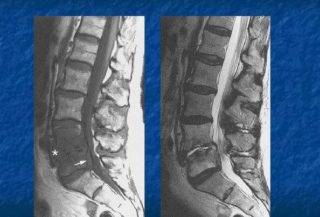

Вертебропластика проводится амбулаторно и без сложной подготовки, но предварительно необходимо пройти обследование с применением КТ/МРТ и другой диагностической аппаратуры, сдать надлежащие лабораторные анализы. Единственное требование – пациент в день операции должен отказаться от еды.

Подготовка предполагает сдачу анализов и прохождение полного медицинского обследования, включая компьютерную и магнитно-резонансную томографию.

Если после вертебропластики у пациента не наблюдается никаких осложнений, спустя сутки его выписывают из стационара домой. В течение реабилитационного периода выздоравливающий должен регулярно посещать врача и контролировать состояние скрепленных позвонков при помощи МРТ и УЗИ.